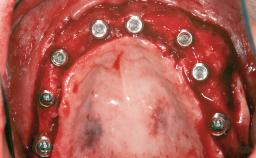

Shell Technique for Horizontal and Vertical Maxillary Bone Augmentation in a Partially Edentulous Patient with Aggressive Periodontal Disease

Bone Augmentation Horizontal|Staged|Vertical

Augmentation Materials Autogenous chips|Autogenous block(s)|Xenogenous